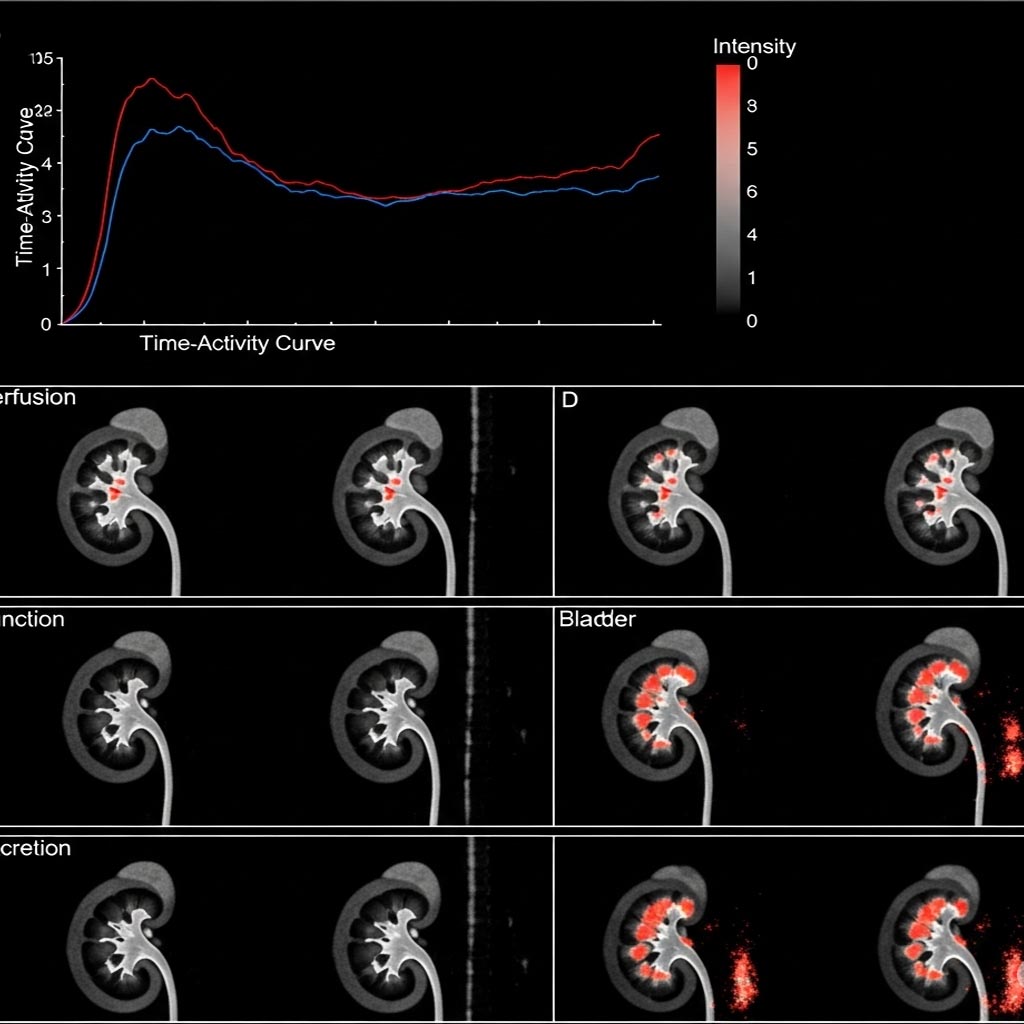

اسکن هسته‌ای کلیه یک روش تصویربرداری پزشکی است که با استفاده از مقدار بسیار کمی ماده رادیواکتیو، عملکرد واقعی کلیه‌ها را بررسی می‌کند. برخلاف سونوگرافی یا سی‌تی‌اسکن که بیشتر ساختار و شکل ظاهری کلیه را نشان می‌دهند، این روش بر ارزیابی عملکرد کلیه‌ها تمرکز دارد. در این اسکن مشخص می‌شود که کلیه‌ها چگونه خون را تصفیه می‌کنند، ادرار را با چه سرعتی تولید و دفع می‌کنند، آیا مسیر خروج ادرار دچار انسداد شده است یا خیر و به طور کلی کلیه‌ها تا چه اندازه وظایف طبیعی خود را به درستی انجام می‌دهند.

• این ماده وارد کلیه‌ها می‌شود و روند رسیدنش، جذبش و خروجش توسط دوربینی به نام «گاما کمرا» ثبت می‌شود.